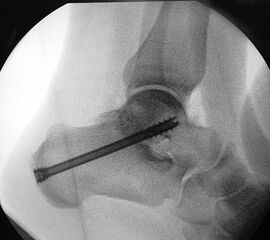

Je nach Operationsziel wird die Arthrodese des Subtalargelenks in verschiedenen Modifikationen durchgeführt. Ist der Rückfuß orthograd ausgerichtet, so erfolgt sie als in situ Fusion, d.h. ohne Korrektur Änderung der Rückfussachse. Liegt eine Rückfuß-Fehlstellung vor, kann diese durch ein additives oder substraktives knöcherndes Vorgehen korrigiert werden 12. Die Fixation der Arthrodese erfolgt üblicherweise mit (kanülierten) Schrauben die über den Tuber calcanei eingebracht werden 3. Eine zweite Schraube zur Sicherung der Rotationsstabilität wird optional über den Processus anterior calcanei im Talushals verankert 4. Der am häufigste verwendete Zugang zum unteren Sprunggelenk verläuft lateral subfibular, alternative Zugänge sind medial oder posterior möglich 56. Ist keine relevante Korrektur notwendig kann der Eingriff auch arthroskopisch durchgeführt werden 78.

Schraubenfehllage: Bei der intra-operative Röntgen-Kontrolle muss der Fuß exakt seitlich und das obere Sprunggelenk ap eingestellt werden, um die korrekte Lage der Schrauben beurteilen zu können.